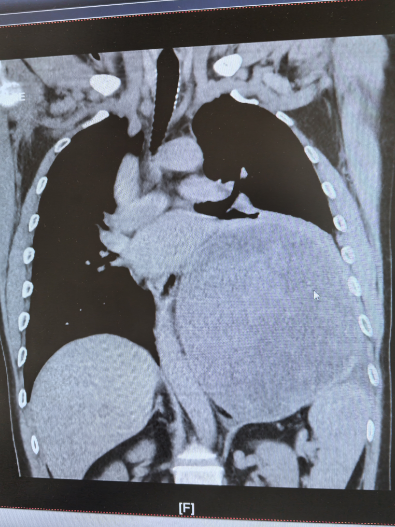

近日,北京天坛医院胸外科团队在多学科协作下,历经4小时,成功为患者完整切除左侧胸腔内直径近19厘米的巨大神经鞘瘤。此次手术的顺利完成,不仅彰显了北京天坛医院胸外科的精湛技术,更体现了多学科协作在疑难重症救治中的关键作用。

家中“顶梁柱”的杜先生,两个月前,左侧卧位时频繁出现心慌、胸痛等症状,当地医院检查后发现,其左后纵隔-胸腔内存在巨大占位性病变。进一步穿刺活检提示为“梭型细胞瘤,结合免疫组化考虑神经鞘瘤”,当地医院虽为其进行了射频消融治疗,暂时缓解了症状,但因肿瘤体积过大、位置特殊,手术切除难度极高,无法开展根治性治疗。

为寻求一线生机,杜先生通过熟人介绍并结合网上查询,慕名找到北京天坛医院胸外科主任医师杨增。医院胸CT检查结果令人揪心,成年人一侧胸腔宽度大约10-15厘米,而杜某的肿瘤直径近19厘米,占据了左侧多半个胸腔,把心脏和主动脉都挤偏了,原本竖直的主动脉已经弯到了右侧。再继续发展,一旦压迫到降主动脉,就会引发急性心衰,随时可能猝死。但更棘手的是,如果进行手术,该肿瘤为实性肿瘤,无任何囊变,血运极其丰富,且与左肺下叶致密粘连,甚至可能累及脊髓,手术中稍有不慎就可能导致心脏骤停、心律失常、大出血、截瘫等严重并发症。“不能因为风险高就放弃患者。”杨增了解情况后,当即决定将患者收入院。